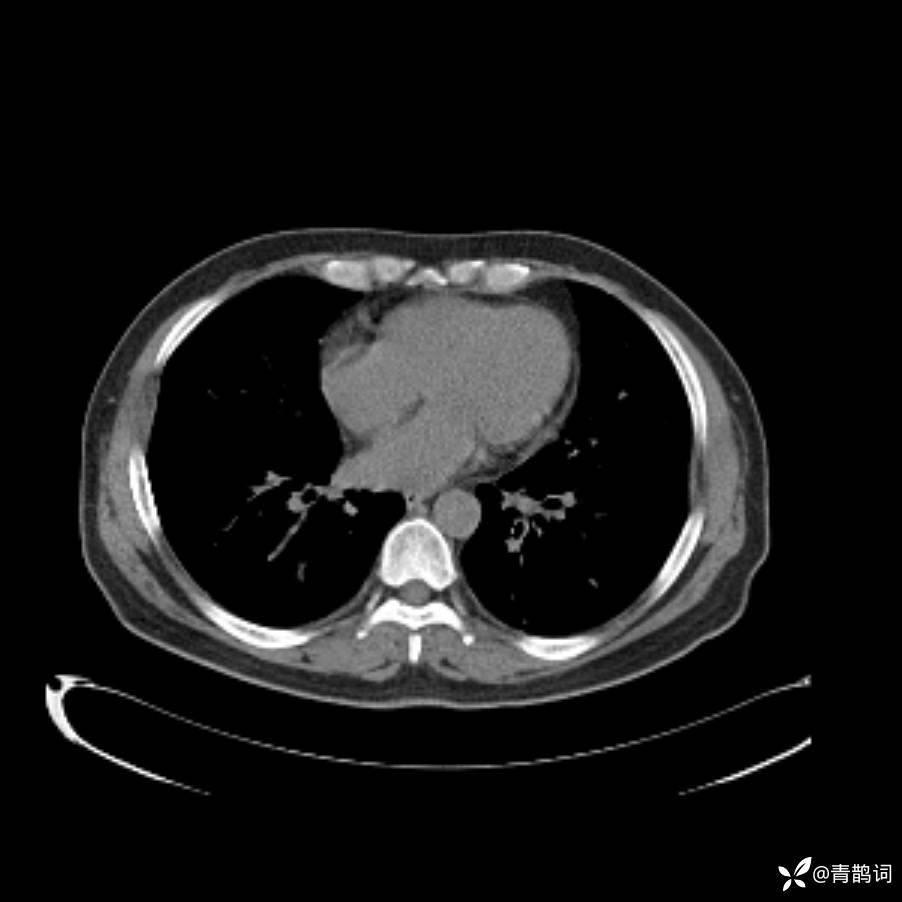

患者年龄:30岁。

患者性别:男。

简要病史:左颜面部肿胀2年,反复咳嗽咳痰,逐渐加重。

结合病史及影像学表现,期待评论区各位老师各抒己见~